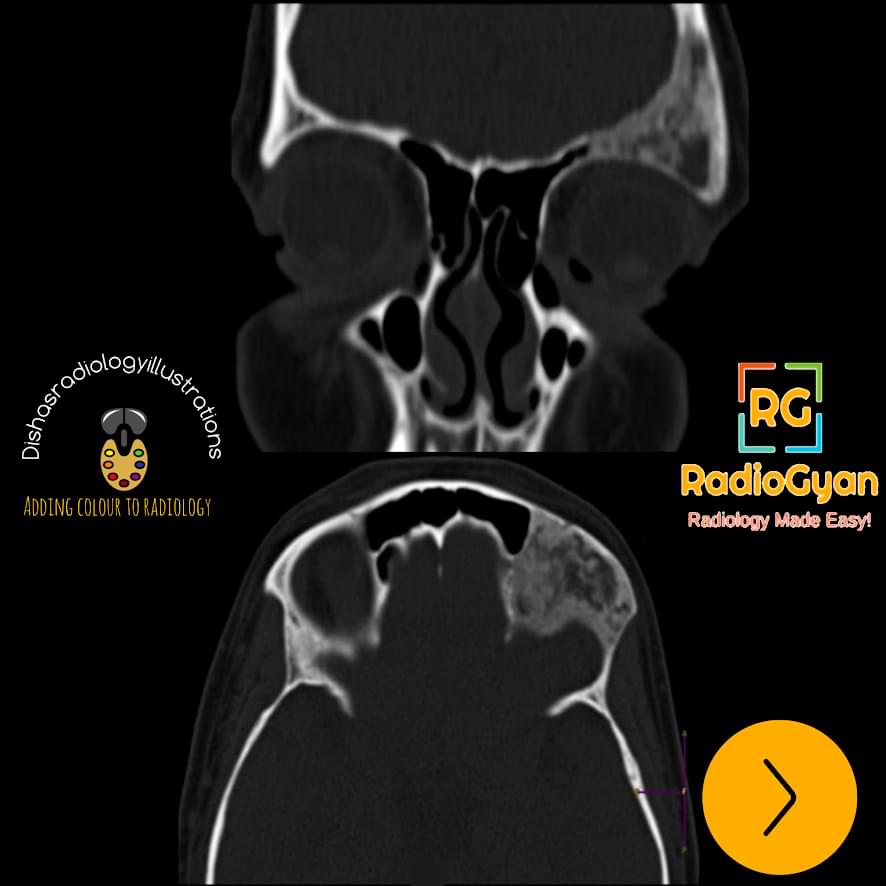

CT Features:

Typical ground-glass appearance as seen on radiographs.